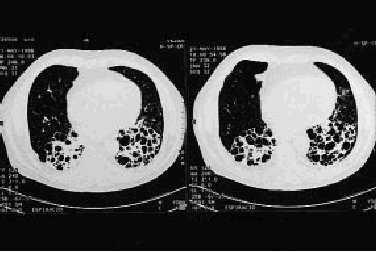

Radiografía simple (Rx) y tomografía axial computarizada (TAC) torácicas: se observan bronquiectasias quísticas intensas que afectan a ambos lóbulos inferiores junto con áreas de enfisema centroacinar en lóbulos superiores.

El paciente presenta bronquiectasias bibasales que cursan con una intensa limitación crónica al flujo aéreo y ligera insuficiencia respiratoria. Actualmente, su tratamiento consiste en medidas higiénico-farmacológicas (fisioterapia respiratoria y antibioterapia), requiriendo mucolíticos y corticoides de forma ocasional. El rigor con el que ha seguido estas prácticas ha contribuido positivamente a su calidad de vida, pues, a pesar de su importante limitación ventilatoria, presenta poca sintomatología con relativa buena tolerancia al esfuerzo.